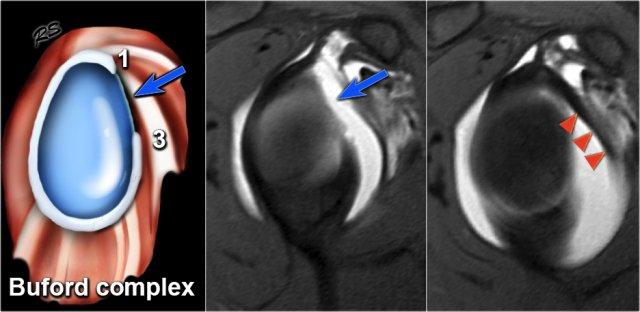

Phức hợp Buford

Phức hợp Buford là một biến thể sụn viền bẩm sinh.

Sụn viền phần trước trên vắng mặt tại vị trí từ 1 đến 3 giờ và dây chằng ổ chảo-cánh tay giữa thường dày lên.

Biến thể này gặp ở khoảng 1,5% dân số.

Trên các hình ảnh cắt ngang này, có thể nhận diện phức hợp Buford.

Sụn viền phía trước vắng mặt tại vị trí từ 1 đến 3 giờ và dây chằng ổ chảo-cánh tay giữa dày lên.

Dây chằng ổ chảo-cánh tay giữa dày lên không được nhầm lẫn với sụn viền bị di lệch.

Luôn có thể truy theo dây chằng ổ chảo-cánh tay giữa lên trên đến bờ ổ chảo và xuống dưới đến xương cánh tay.